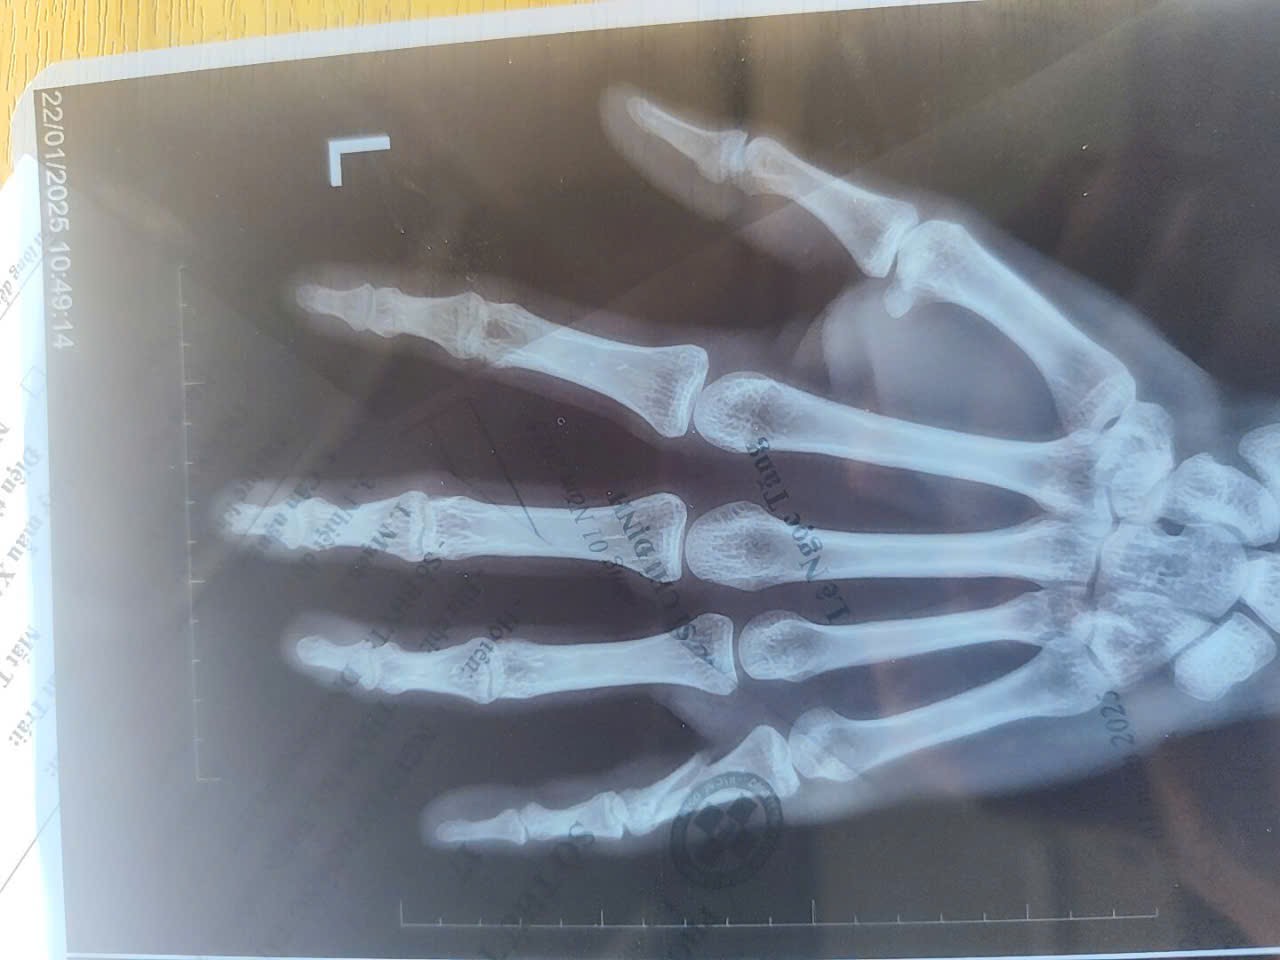

Dạ chào bác sĩ, mình có bị gãy ngón tay út đốt thứ 3, có đi khám và được bó bột, nhưng do lý do riêng nên khoảng tầm 27 ngày sau khi bó bột thì mình có tự tháo bột ra và khi mình đi khám chụp x quang lại thì ngón tay vẫn còn gãy, hiện tại mình đang dùng nẹp cố định lại. Vậy cho mình hỏi khoảng tầm bao lâu thì ngón tay mình mới lành xương vậy ạ, và việc dùng nẹp thay cho bó bột có gây ảnh hưởng gì không

Chào em. Bản chất dùng nẹp hay bó bột đều tránh em vận động gây di lệch ổ gãy, Sau 1 tháng nữa em chụp lại phim. Em không nên vận động nhiều bàn tay bị thương